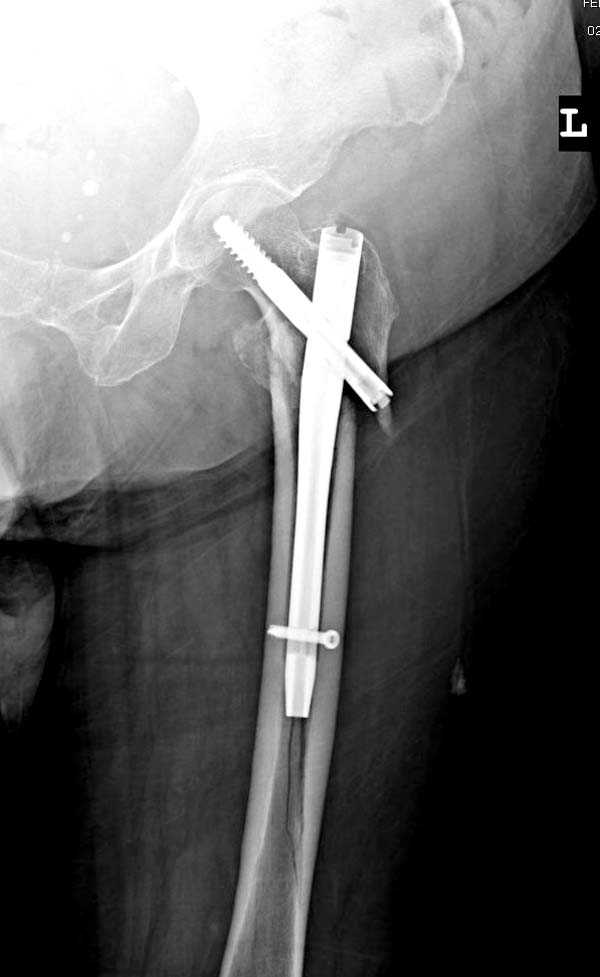

При первом послеоперационном поликлиническом осмотре больная предъявила жалобы на боли в бедре. В серийных снимках обнаружен продольный перелом верхнего отдела бедра.

Считаем, что техническая ошибка произошла во время установки гвоздя, когда рассверливанию канала не уделили должного внимания. Канал остался узковат, и гвоздь был забит с силой. Полная нагрузка конечности приостановлена на две недели, и боли в конечности изчезли. Больная начала нагрузку и перелом срастается.-- Djoldas Kuldjanov, M.D.Associate ProfessorDepartment of Orthopedic SurgerySt. Louis University

Мне тоже представляется, что это не единственная проблема. Продольные трещины заживают легко и быстро. Интересно, почему увеличился варус и

появилась медиализация дистального отломка.

Мне думается, что варусное положение проксимального отломка на последующих снимках не более чем проекционный феномен. Раскол же диафиза вдоль, наверняка, связан с чрезмерно насильственным введением штифта. Вообще, при реверсивных, да и обычных вертельных переломах, многие давно отказались от короткой Гаммы в пользу long-версии. Но в любом случае надо быть на 100 уверенным в подготовке канала.